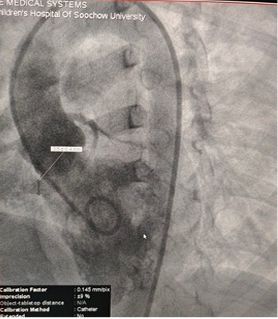

Case Sharing | Successful Closure of Multi-Exit Membranous Septal Aneurysm-Type VSD Using MemoSorb Biodegradable Occluder

Pomyślne zamknięcie multi-Exit Membranous Septal Aneurysm-Type VSD przy użyciu MemoSorb W pełni biodegradowalnego Okludera

Średnica podstawy: ~ 6,1mm z wieloma punktami wyjścia

Tkanka podobna do błony obserwowana nad defektem

Kolor Dopplera: przepływ bocznikowy od lewej do prawej

Diagnoza: VSD okołobniaste

Wyzwanie: Wielokrotne wyjścia z delikatnej tkanki błonowej

Selected MemoSorb ABFDQ-II 9 occluder based on intraoperative angiography and echocardiographic assessment.